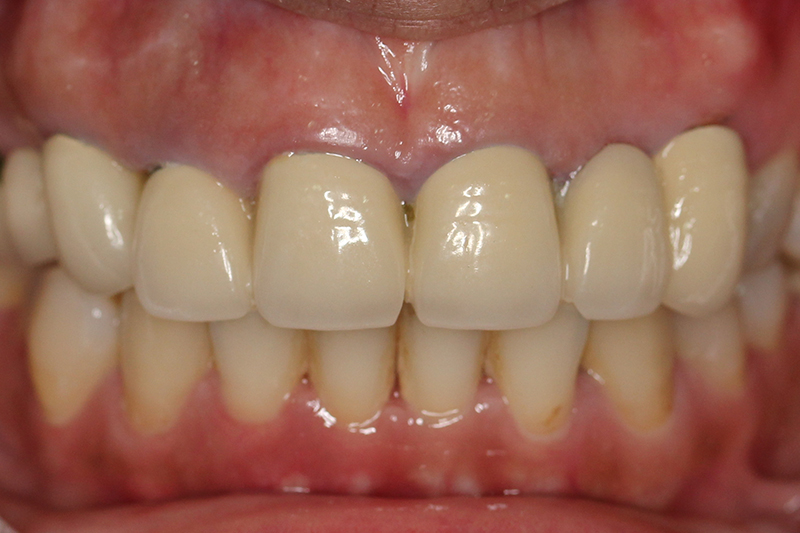

缺牙多顆

案例一

術後